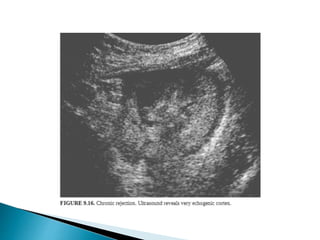

On a grey scale :

With acute transplant rejection may show an

1. increase in the volume of the kidney

2. Swelling

3. Altered echogenicity of the renal pyramids and the

cortex.

The high echogenicity of the sinus of a normal kidney may be diminished.

These findings are thought to reflect edema of the parenchyma and of the

renal sinus fat. Edema of the collecting system walls may make them appear

thickened.

The sensitivity of these findings to diagnose rejection, however, and the

ability to distinguish rejection from cyclosporine nephrotoxicity and ATN

when the findings are not clearly present are poor